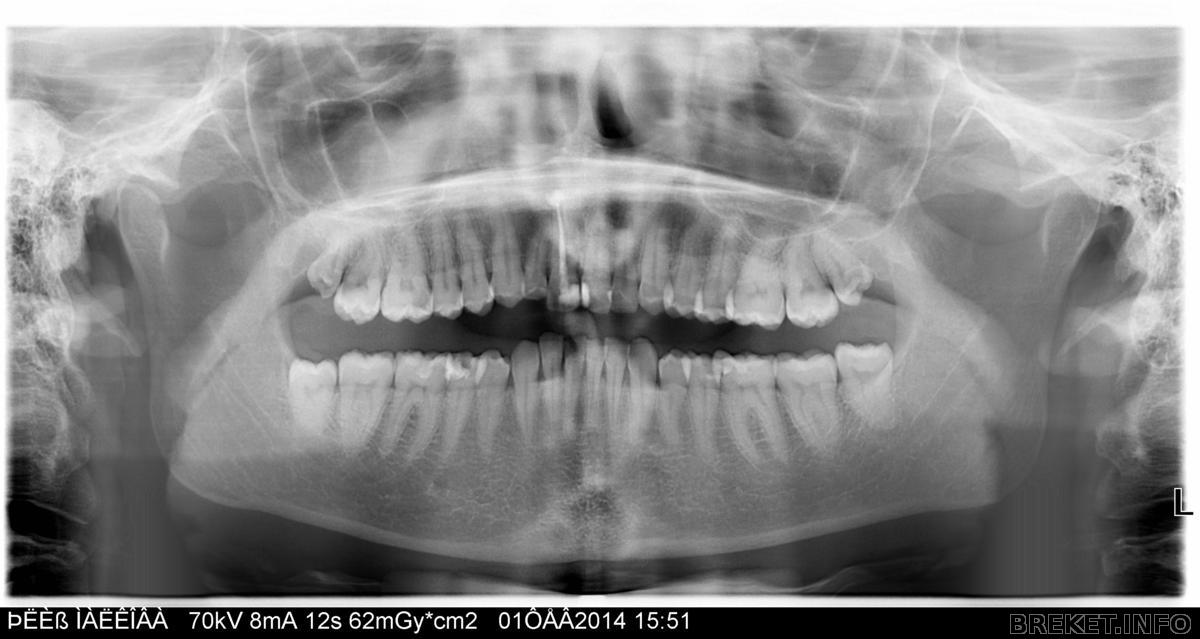

Я сделала панорамный снимок, вот он:

Прокомментируйте, пожалуйста, кто в этом понимает!